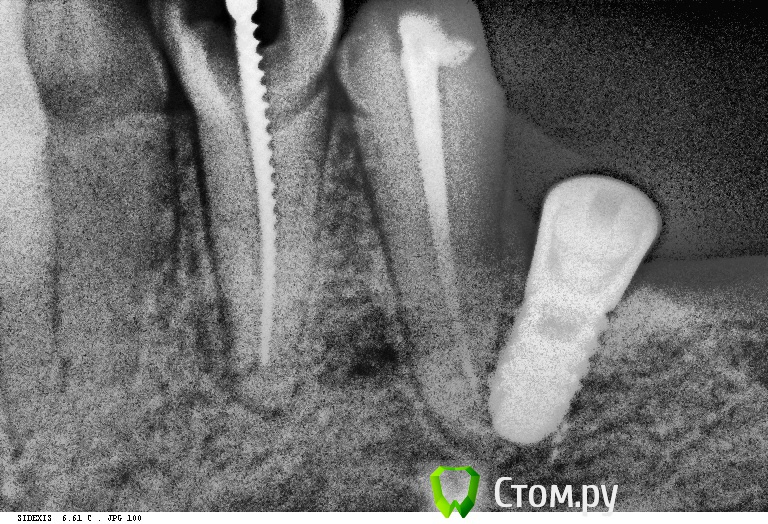

StomDoc Опубликовано 15 ноября, 2013 Поделиться Опубликовано 15 ноября, 2013 Что делать если имплантат установлен по касательной к зубу??? Даже немного перфорировав его??? Сегодня сделаю снимок!! Имплант убиратьь или если нет симптомов то оставить????есть у кого нибудь подобный опыт?? Ссылка на комментарий

sergio Опубликовано 15 ноября, 2013 Поделиться Опубликовано 15 ноября, 2013 Что делать если имплантат установлен по касательной к зубу??? Даже немного перфорировав его??? Сегодня сделаю снимок!! Имплант убиратьь или если нет симптомов то оставить????есть у кого нибудь подобный опыт??Сначала точно убедитесь в касании по 3 прицелам: орторадиальная,медиальная и дистальная проекции Ссылка на комментарий

x3m Опубликовано 20 ноября, 2013 Поделиться Опубликовано 20 ноября, 2013 Что делать если имплантат установлен по касательной к зубу??? Даже немного перфорировав его??? в посте №9 снимок этого случая?тогда ничего не понимаю - разве имплантат перфорирует корень или находится по касательной?там же видно расстояние между ними - добрых 1,5 (апикально)-2 (коронарно) мм. офф.В лунке пальпируется верхушка винта....или у Вас тонкие пальцы, или было очень травматичное удаление Ссылка на комментарий